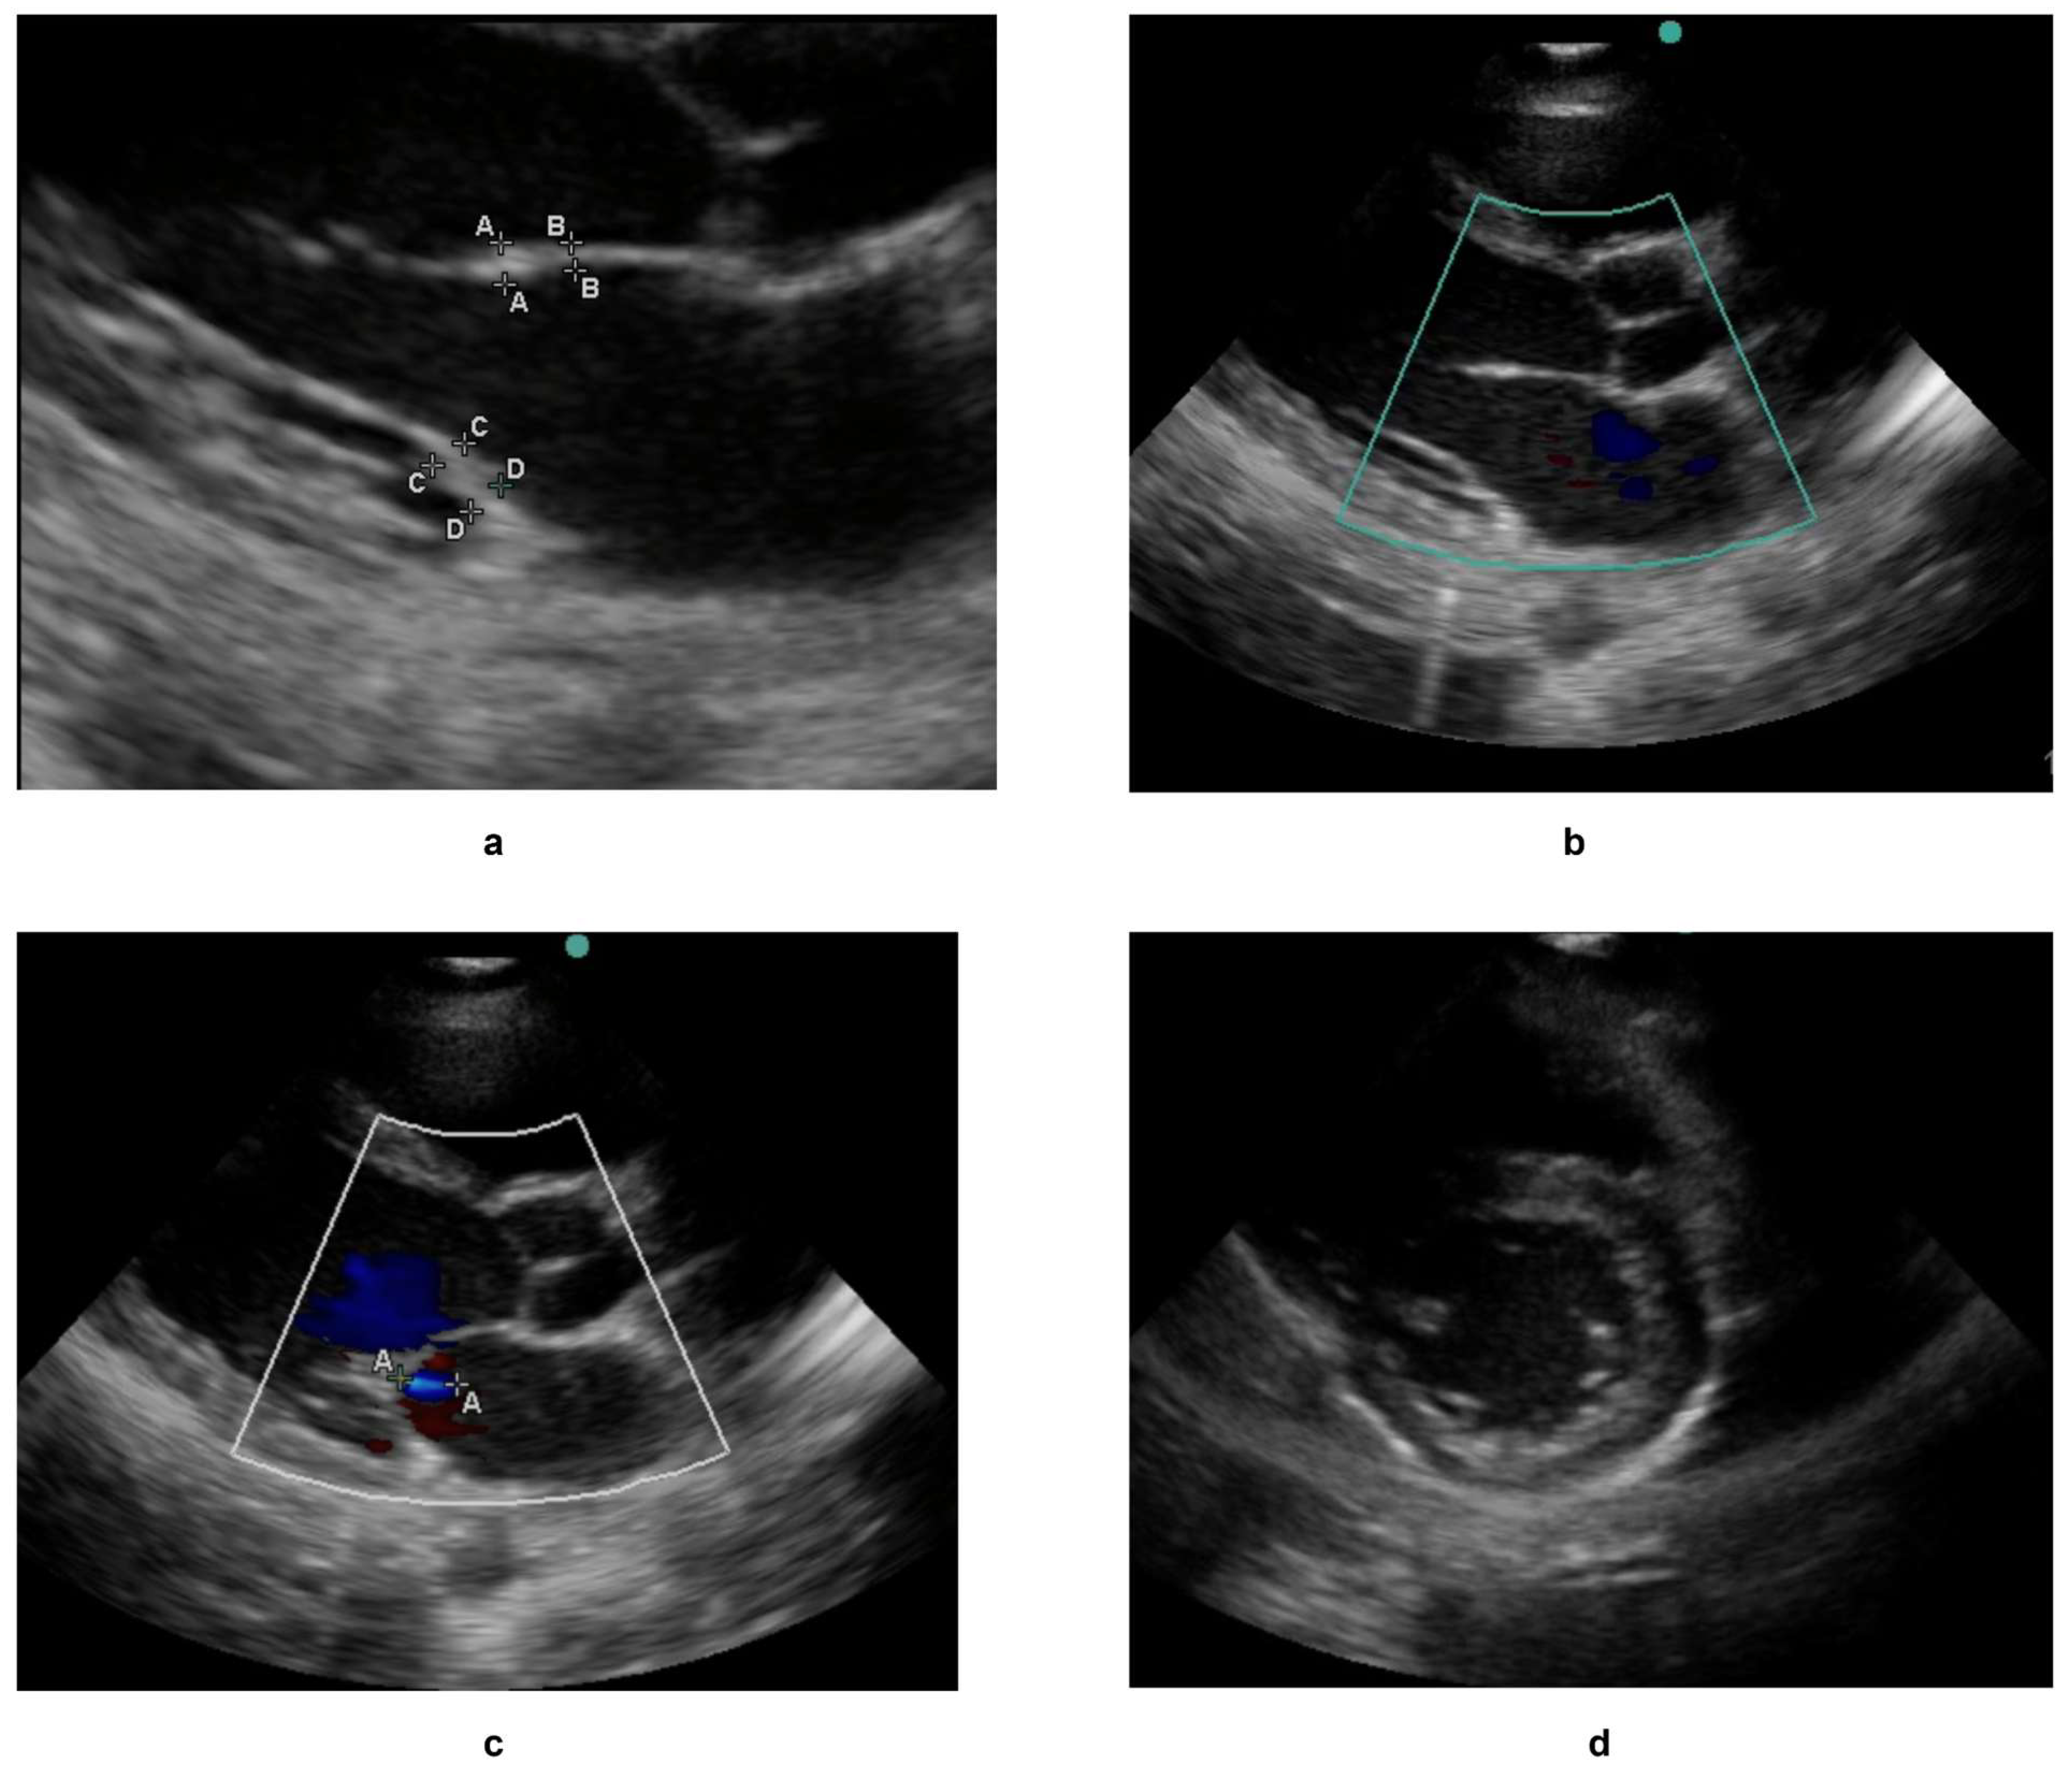

The large unlabelled subset was used to pre-train self-supervised models (SimCLR and DINOv2) to learn general representations of echocardiographic features. The labelled subset was then partitioned into training (70%), validation (15%), and test sets (15%) for supervised fine-tuning in order to detect and classify RHD-induced valvular pathologies. This combined approach—leveraging unlabelled data for pretraining and labelled data for task-specific refinement—ensured robust model performance. Sample images from the dataset are shown in Figure 4 and corresponding labels are shown in Table 1.

Figure 4.

A sample of echocardiograms used as part of the labelled dataset, with the corresponding labels of all four images shown in Table 1. (a–c) are echocardiograms with a parasternal long axis view while (d) is an echo with a parasternal short axis view. The thickness state, RHD condition if any, and the severity of RHD condition if present have also been shown in Table 1. The uppercase letters, such as A–A or B–B denote standardized measurement points for structures such as valve thickness.

Table 1.

Sample annotations from the Echo Label application, showing the captured metadata for various echocardiogram files.